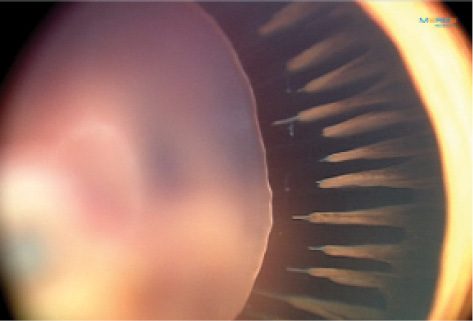

Ultrawide-field imaging enables us to record retinal images for diagnosis and follow-up in both cooperative and uncooperative infants. In our clinic we capture anterior segment and fundus images with the RetCam3 Ophthalmic Imaging System (Natus Medical) and the Daytona digital, nonmydriatic, ultra-widefield scanning laser ophthalmoscope (Optos). We have recently incorporated some newer equipment, such as the PanoCam (Visunex Medical Systems) and ICON (Phoenix Clinical) retinal cameras, into our practice. Some of these devices can capture fluorescein and indocyanine green angiography images (Figures 1 and 2). They can also document the clinical picture and provide specific data about disease progression before and after surgery.7,8

Figure 2. RetCam3 image of the eye of a 4-year-old boy born at 41 weeks with a subluxated cataractous crystalline lens, persistent fetal vasculature, and coloboma. Remarkably elongated ciliary process is seen here prior to surgery.